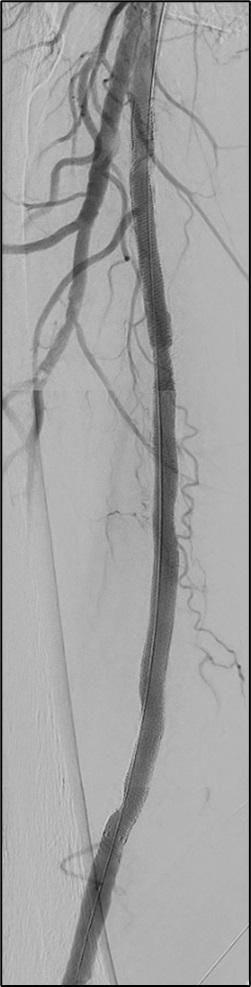

The SUNDAY trial is a clinical study investigating the best treatment approach for patients with uncomplicated TBAD. It is a randomised, open-label trial conducted across the Nordic countries, including Denmark, Sweden, Norway, Finland, and Iceland.

The trial compares two treatment strategies for uncomplicated TBAD patients: standard medical therapy (SMT) alone versus SMT combined with thoracic endovascular aortic repair (TEVAR). SMT typically involves controlling blood pressure and providing pain relief, with β-blockers as first-line treatment.

The primary aim of the SUNDAY trial is to determine whether the addition of TEVAR improves fiveyear survival rates compared to SMT alone. Secondary outcomes include aortic-related mortality, neurological events, quality of life, reinterventions,

and healthcare costs. The trial aims to enrol around 554 patients and follow them for up to five years. The trial design is pragmatic, meaning it tries to reflect real-world practices by allowing flexibility in the type of TEVAR procedure performed and SMT management based on local protocols.

This study seeks to address a crucial question: does early intervention with TEVAR offer significant survival benefits in uncomplicated cases of TBAD? Previous research suggested potential benefits, but larger, randomised trials like SUNDAY are needed to provide definitive answers.